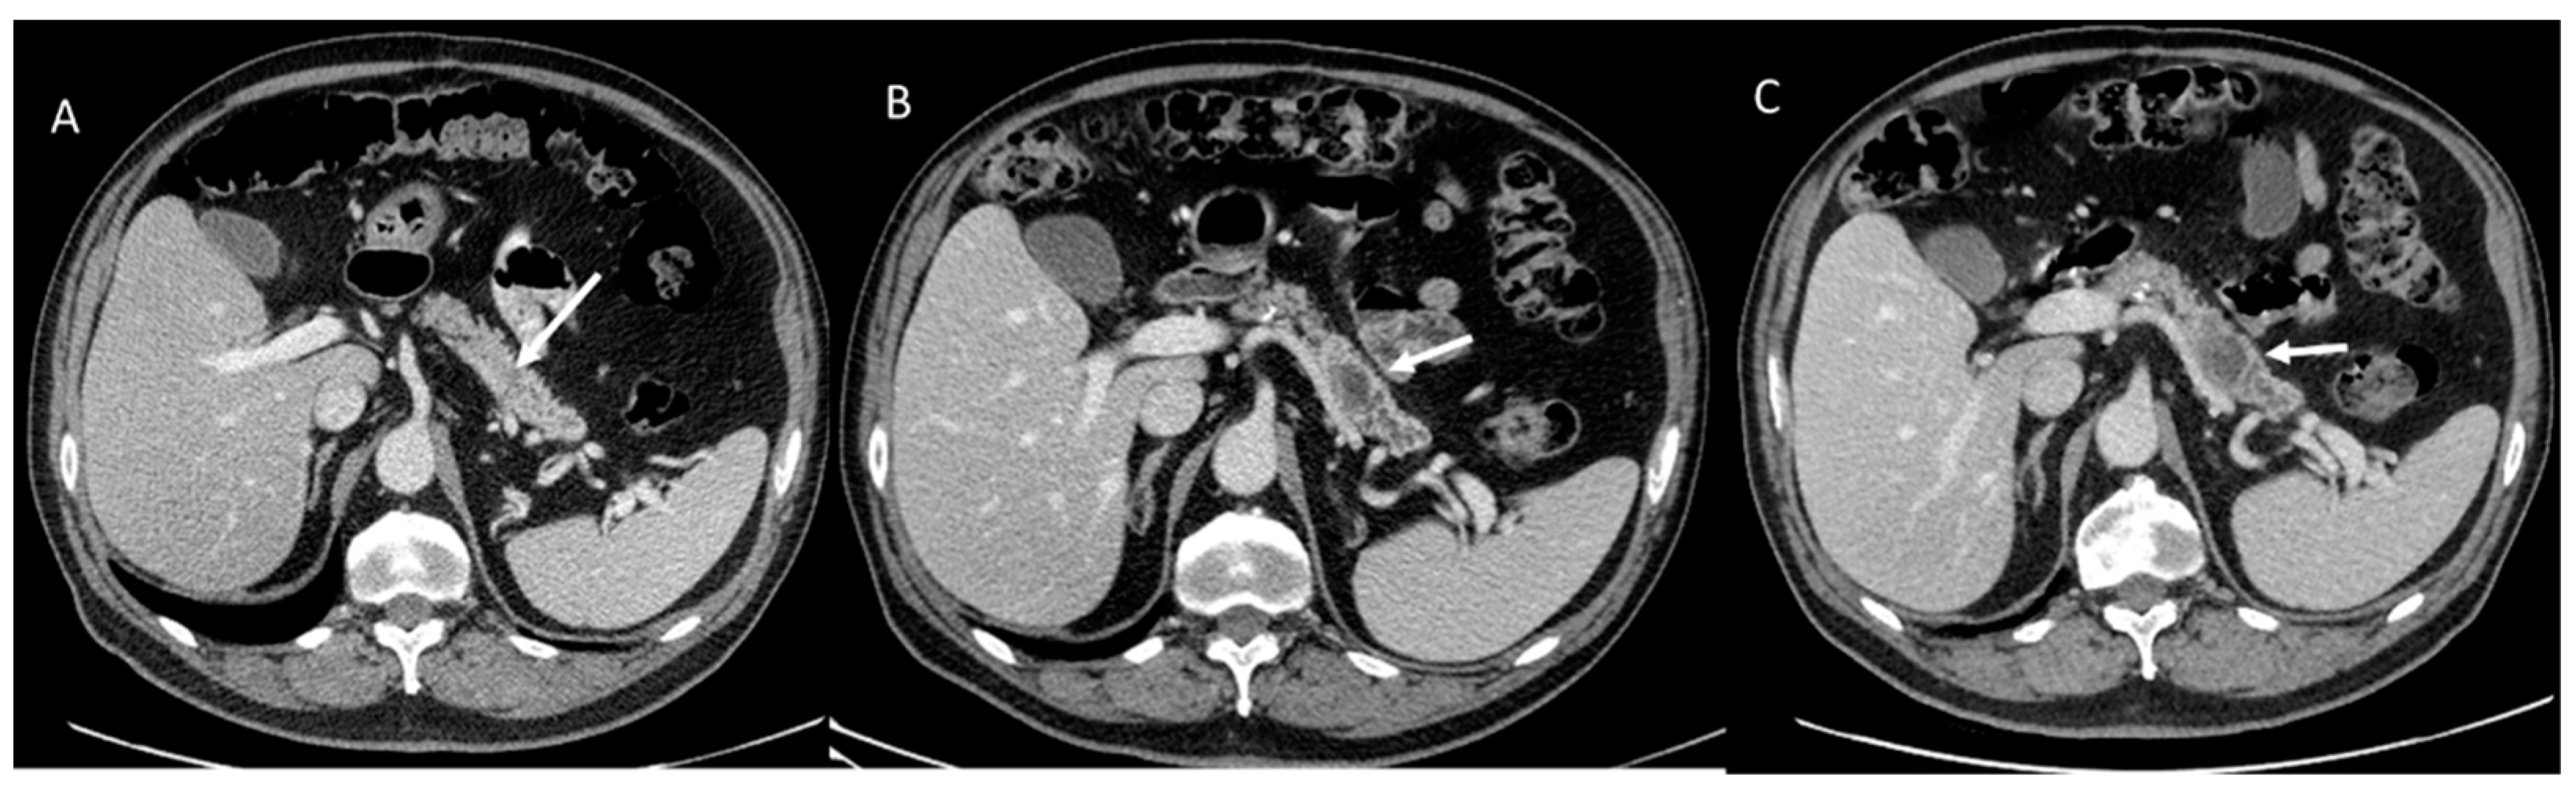

- Granata, V.; Fusco, R.; Catalano, O.; Setola, S.V.; Castelguidone, E.D.L.D.; Piccirillo, M.; Palaia, R.; Grassi, R.; Granata, F.; Izzo, F.; et al. Multidetector computer tomography in the pancreatic adenocarcinoma assessment: An update. Infect. Agents Cancer 2016, 11, 57. [Google Scholar] [CrossRef]

- Bartoli, M.; Barat, M.; Dohan, A.; Gaujoux, S.; Coriat, R.; Hoeffel, C.; Cassinotto, C.; Chassagnon, G.; Soyer, P. CT and MRI of pancreatic tumors: An update in the era of radiomics. JPN. J. Radiol. 2020, 38, 1111–1124. [Google Scholar] [CrossRef]

- Treadwell, J.R.; Mitchell, M.D.; Eatmon, K.; Jue, J.; Zafar, H.; Teitelbaum, U.; Schoelles, K. Imaging Tests for the Diagnosis and Staging of Pancreatic Adenocarcinoma: A Meta-Analysis. Pancreas 2016, 45, 789–795. [Google Scholar] [CrossRef]

- Chaudhari, V.V.; Raman, S.S.; Vuong, N.L.; Zimmerman, P.; Farrell, J.; Reber, H.; Sayre JLu, D.S.K. Pancreatic cystic lesions: Discrimination accuracy based on clinical data and high resolution CT features. J. Comput. Assist. Tomogr. 2007, 31, 860–867. [Google Scholar] [CrossRef] [PubMed]

- Granata, V.; Grassi, R.; Fusco, R.; Galdiero, R.; Setola, S.V.; Palaia, R.; Belli, A.; Silvestro, L.; Cozzi, D.; Brunese, L.; et al. Pancreatic cancer detection and characterization: State of the art and radiomics. Eur. Rev. Med. Pharmacol. Sci. 2021, 25, 3684–3699. [Google Scholar] [CrossRef] [PubMed]